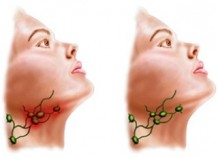

На фото зниження висоти зубодесневого кріплення на ½ висоти кореня

На фото - запальні кровоточивість, почервоніння ясен, які викликали оголення коренів зубів